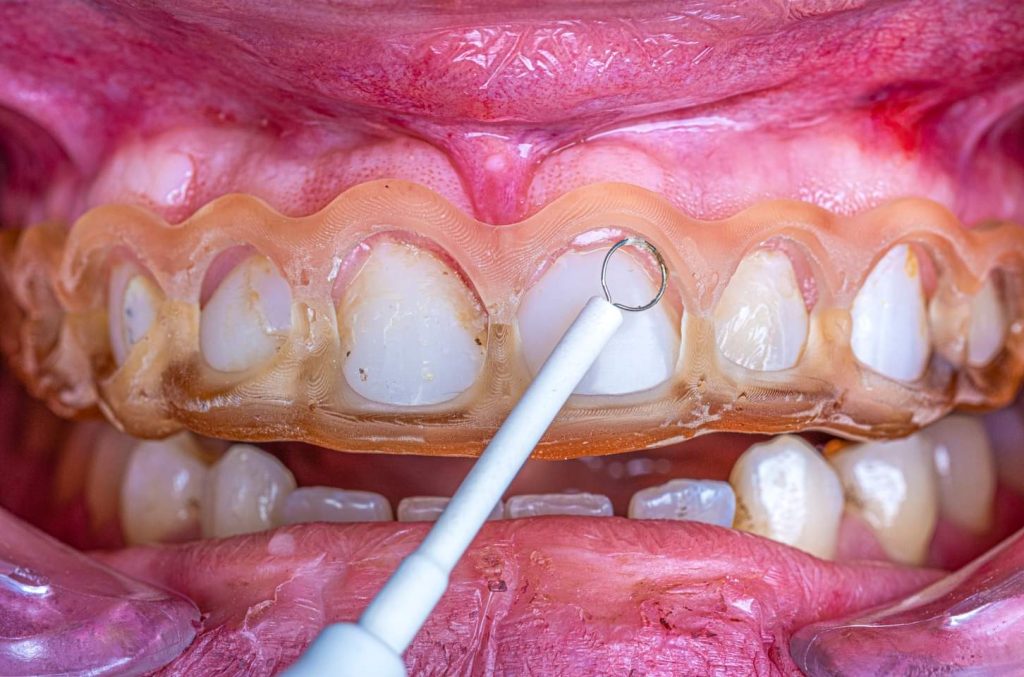

The case presented in this case report is for a 27-years-old female patient with a chief complaint of aesthetic correction for her smile. The patient was unhappy with her smile. After clinical examination, there were previous old composite veneering done poorly and incorrectly to close the multiple interdental spacing. After discussing the various treatment options (i.e., orthodontic treatment, direct, or indirect veneers), indirect ceramic veneering was selected. The step-by-step treatment protocol is presented in the images below.